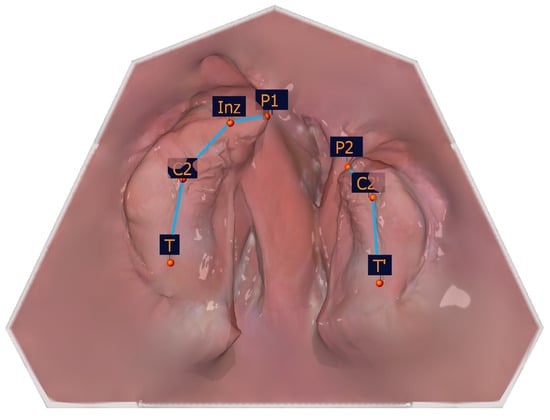

The selection of the measuring points detailed in Table 1 was based on a number of factors, including the publications of Mazaheri et al. [18], Ashley-Montagu [19], Sillman [20], and Robertson [21]. If a point appears on both jaw segments, a ′ indicates that the point is located on the smaller jaw segment. Figure 4 and Table 1 show the measuring points on a dental left-sided cleft lip and palate model.

Figure 4. Illustration of the anatomical measuring points. The anatomical measuring points and their description are presented in Table 1.